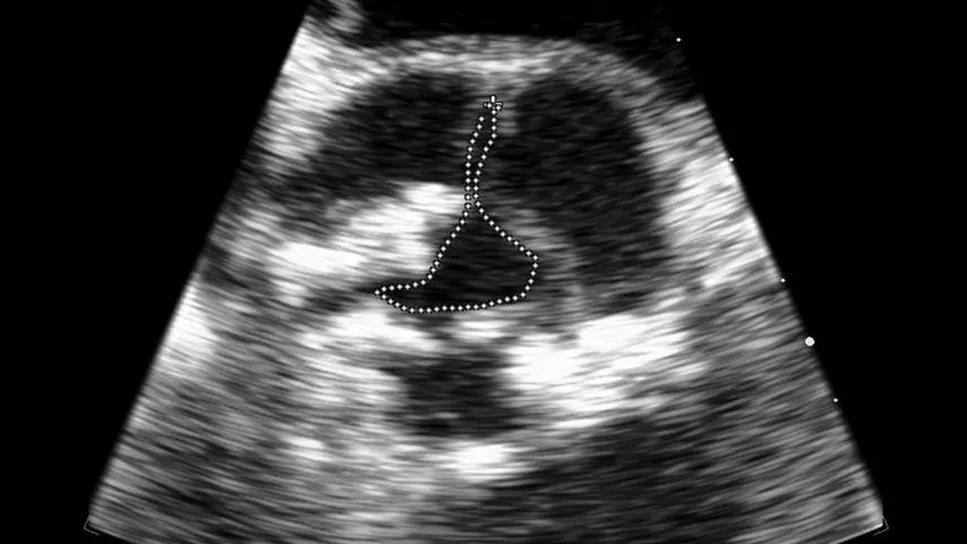

echocardiogram showing severe aortic stenosis

Figure 2. Severe aortic stenosis planimetry on transesophageal echocardiography.